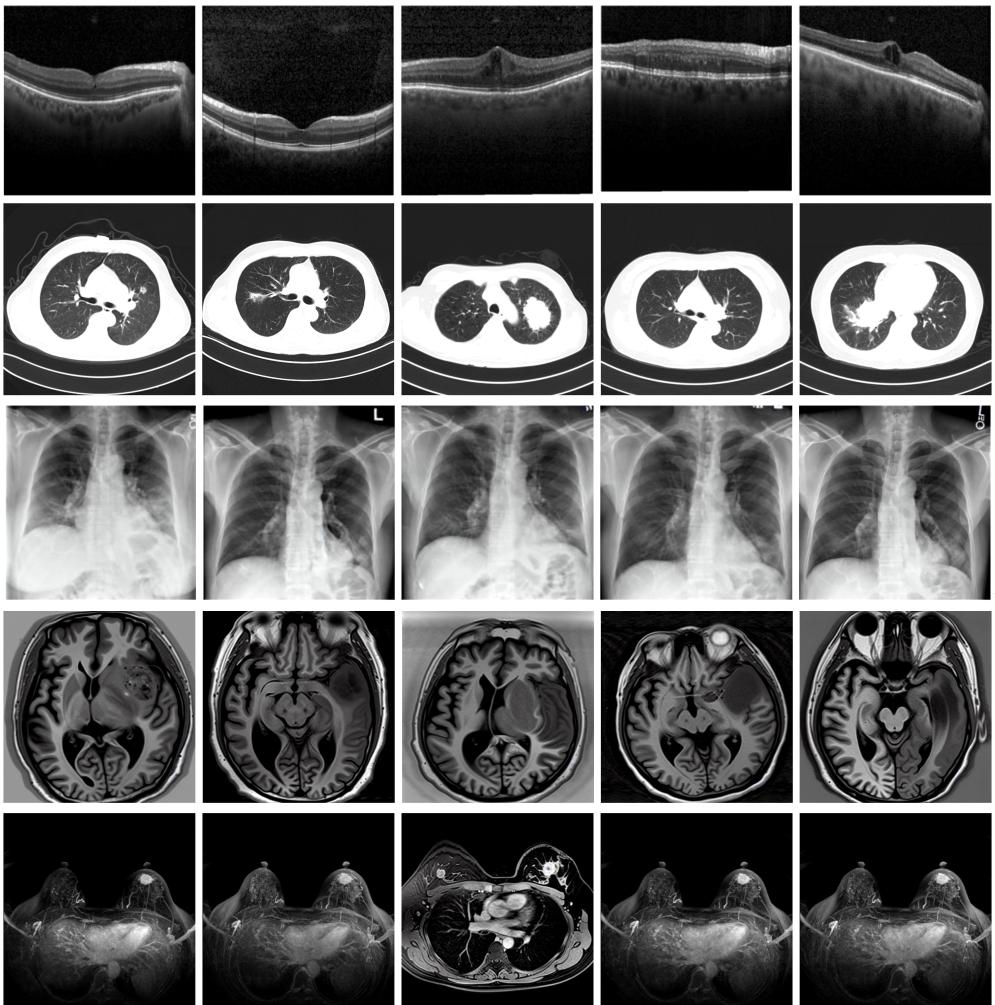

圖為由MINIM生成的高質(zhì)量醫(yī)學(xué)合成圖像(受訪者供圖)

“目前公開的醫(yī)學(xué)影像數(shù)據(jù)非常有限,我們建立的生成式模型有望解決訓(xùn)練數(shù)據(jù)不夠的問題?!北本┐髮W(xué)未來技術(shù)學(xué)院助理研究員王勁卓說,研究團(tuán)隊(duì)利用多種器官在CT、X光、磁共振等不同成像方式下的高質(zhì)量影像文本配對數(shù)據(jù)進(jìn)行訓(xùn)練,最終生成海量的醫(yī)學(xué)合成影像,其在圖像特征、細(xì)節(jié)呈現(xiàn)等多方面都與真實(shí)醫(yī)學(xué)圖像高度一致。

實(shí)驗(yàn)結(jié)果顯示,MINIM生成的合成數(shù)據(jù)在醫(yī)生主觀評測指標(biāo)和多項(xiàng)客觀檢驗(yàn)標(biāo)準(zhǔn)方面達(dá)國際領(lǐng)先水平,在臨床應(yīng)用中具有重要參考價值。在真實(shí)數(shù)據(jù)基礎(chǔ)上,使用20倍合成數(shù)據(jù)在眼科、胸科、腦科和乳腺科的多個醫(yī)學(xué)任務(wù)準(zhǔn)確率平均可提升12%至17%。